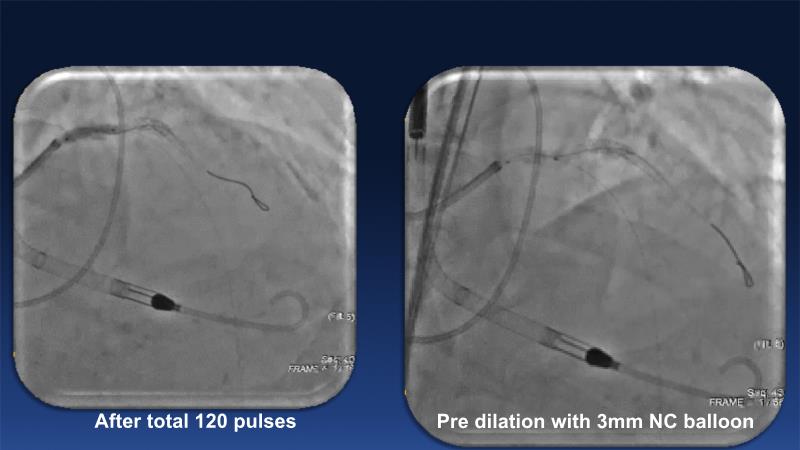

Revolutionising coronary calcium treatment: unleashing the potential of intravascular lithotripsy

Over the last five years, we have learned that there is a new tool for treating calcium, the greatest enemy of interventional cardiology, which can take various forms: intravascular lithotripsy. In this session, look at how to master this technique in different scenarios, from eccentric calcified lesions to left main bifurcations.

- To understand the mechanism of action of intravascular lithotripsy (IVL) for the treatment of calcified lesions

- To uncover practical tips and techniques for IVL in challenging calcified lesions: eccentric calcified lesions